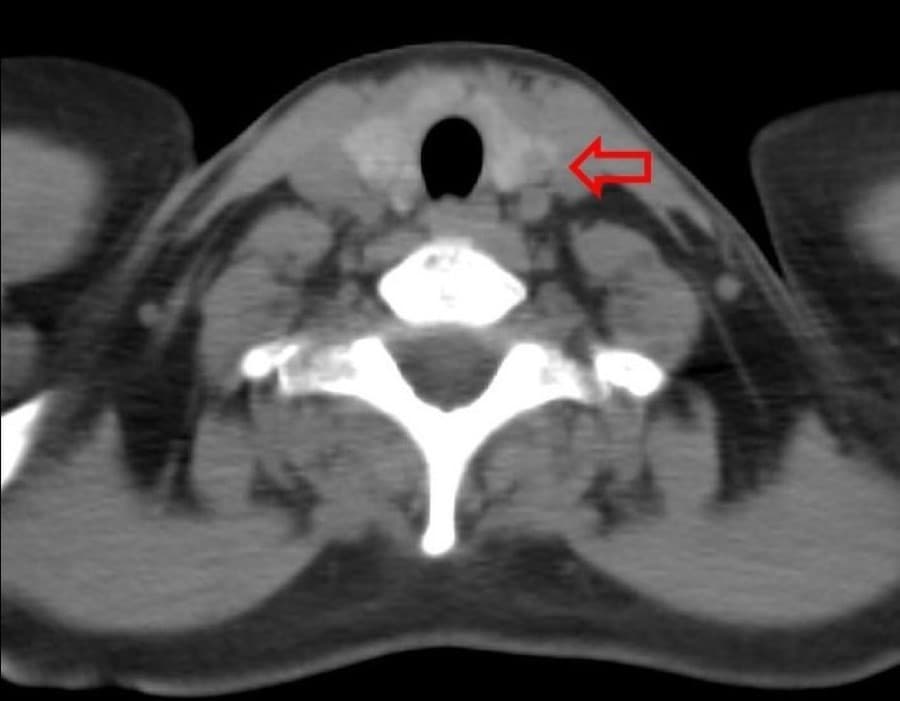

In complex cases, we may recommend CT scans, MRI, or PET scans to evaluate the mass's relationship to surrounding structures or detect potential spread. These advanced imaging modalities provide three-dimensional views of the neck anatomy and are particularly valuable for surgical planning in malignant cases.